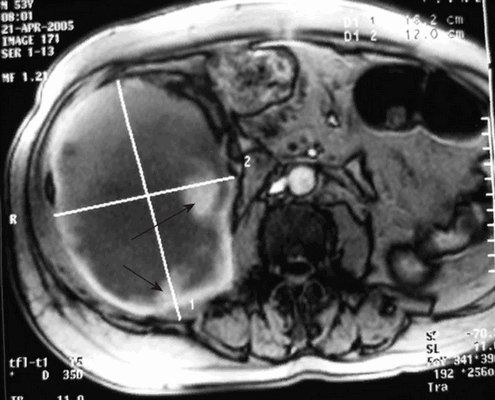

Гигантская гематома на фоне приема гепариноподобных препаратов на МР-скане (вторичные кровоизлияния указаны черными стрелками)

- Травмы. Забрюшинная гематома формируется при прямом ударе в область поясницы или живота, дорожно-транспортном происшествии, падении с высоты. Часто сочетается с переломами костей и другими повреждениями. В экстренных ситуациях с выраженными клиническими проявлениями приоритетным исследованием остается компьютерная томография из-за быстроты получения результатов. КТ-сканы лучше в оценке кровотечений и переломов. МРТ может показать скрытые повреждения костей, связочного аппарата и пр.